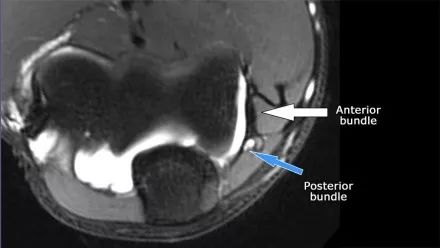

在研究韧带时,尤其是UCL,始终使用轴向图像。如果你看内侧上髁,你会发现后束是一个薄的结构(蓝色箭头)。注意在肘管内的尺神经。

后束形成肘管隧道的地板。支持带覆盖肘管。请注意,前束更厚(白色箭头)。您可以看到前韧带和后韧带之间的区别,即使它们形成一条韧带。走向远端,我们会看到它们合并在一起以附着于崇高的结节。